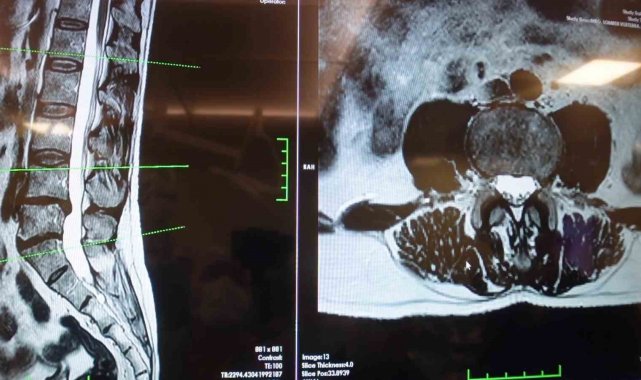

Elazığ Fırat Üniversitesi Hastanesi Beyin ve Sinir Cerrahisi Anabilim Dalı Başkanı Prof. Dr. Fatih Serhat Erol, bel fıtığı hastalığı hakkında açıklamalarda bulundu. Beyin ve sinir cerrahisi pratiğinde sık karşılaşılan hasta gruplarından birinin omurga hastaları olduğunu belirten Prof. Dr. Erol, "Boyun ve sırt omurlarının yanı sıra en çok bel bölgesiyle ilgili sorunlar görülüyor. Bel fıtığı önemli bir hastalıktır. Bel ağrılarının büyük bir kısmının bel fıtığından değil, mekanik bel ağrısından kaynaklanıyor. Mekanik bel ağrısının kaslar, eklemler, iskelet sistemi ve bu yapıları birbirine bağlayan bağların uzun süreli zorlanması sonucu ortaya çıkmaktadır. Bu durumun hastalarda şiddetli bel ağrısına neden olabilir. Mekanik bel ağrısının bel fıtığı ile karıştırılmaması gerekiyor. Bel fıtığına kıyasla mekanik bel ağrıları çok daha sık görülüyor. Bir diğer önemli hasta grubu ise omurilik kanal darlığı olan hastalardır. Bu hastalıkta dejeneratif süreçler sonucunda omurilik kanalında ve sinir köklerinin geçtiği kemik kanallarda daralma ve kireçlenme meydana geliyor. Bu durumun omurilik ve sinir köklerinde sıkışmaya yol açar. Hastaların ayakta dururken ya da yürürken bel, kalça ve bacaklara yayılan şiddetli ağrılar hissettiğini, yürüyüş mesafesi arttıkça oturup dinlenme ihtiyacı duyarlar. Tedavi sürecinin doğru tanıya göre belirleniyor. Bel ve bacak ağrısı şikayeti olan hastaların mutlaka bir beyin ve sinir cerrahisi uzmanına başvurması gerekiyor. Hastaların şikayetlerinin dinlenmesi, gerekli muayene ve tetkiklerin yapılmasının ardından hastalıkların birbirinden ayırt edilebildiğini ve buna uygun tedavi planının oluşturulur" cümlelerini kullandı.